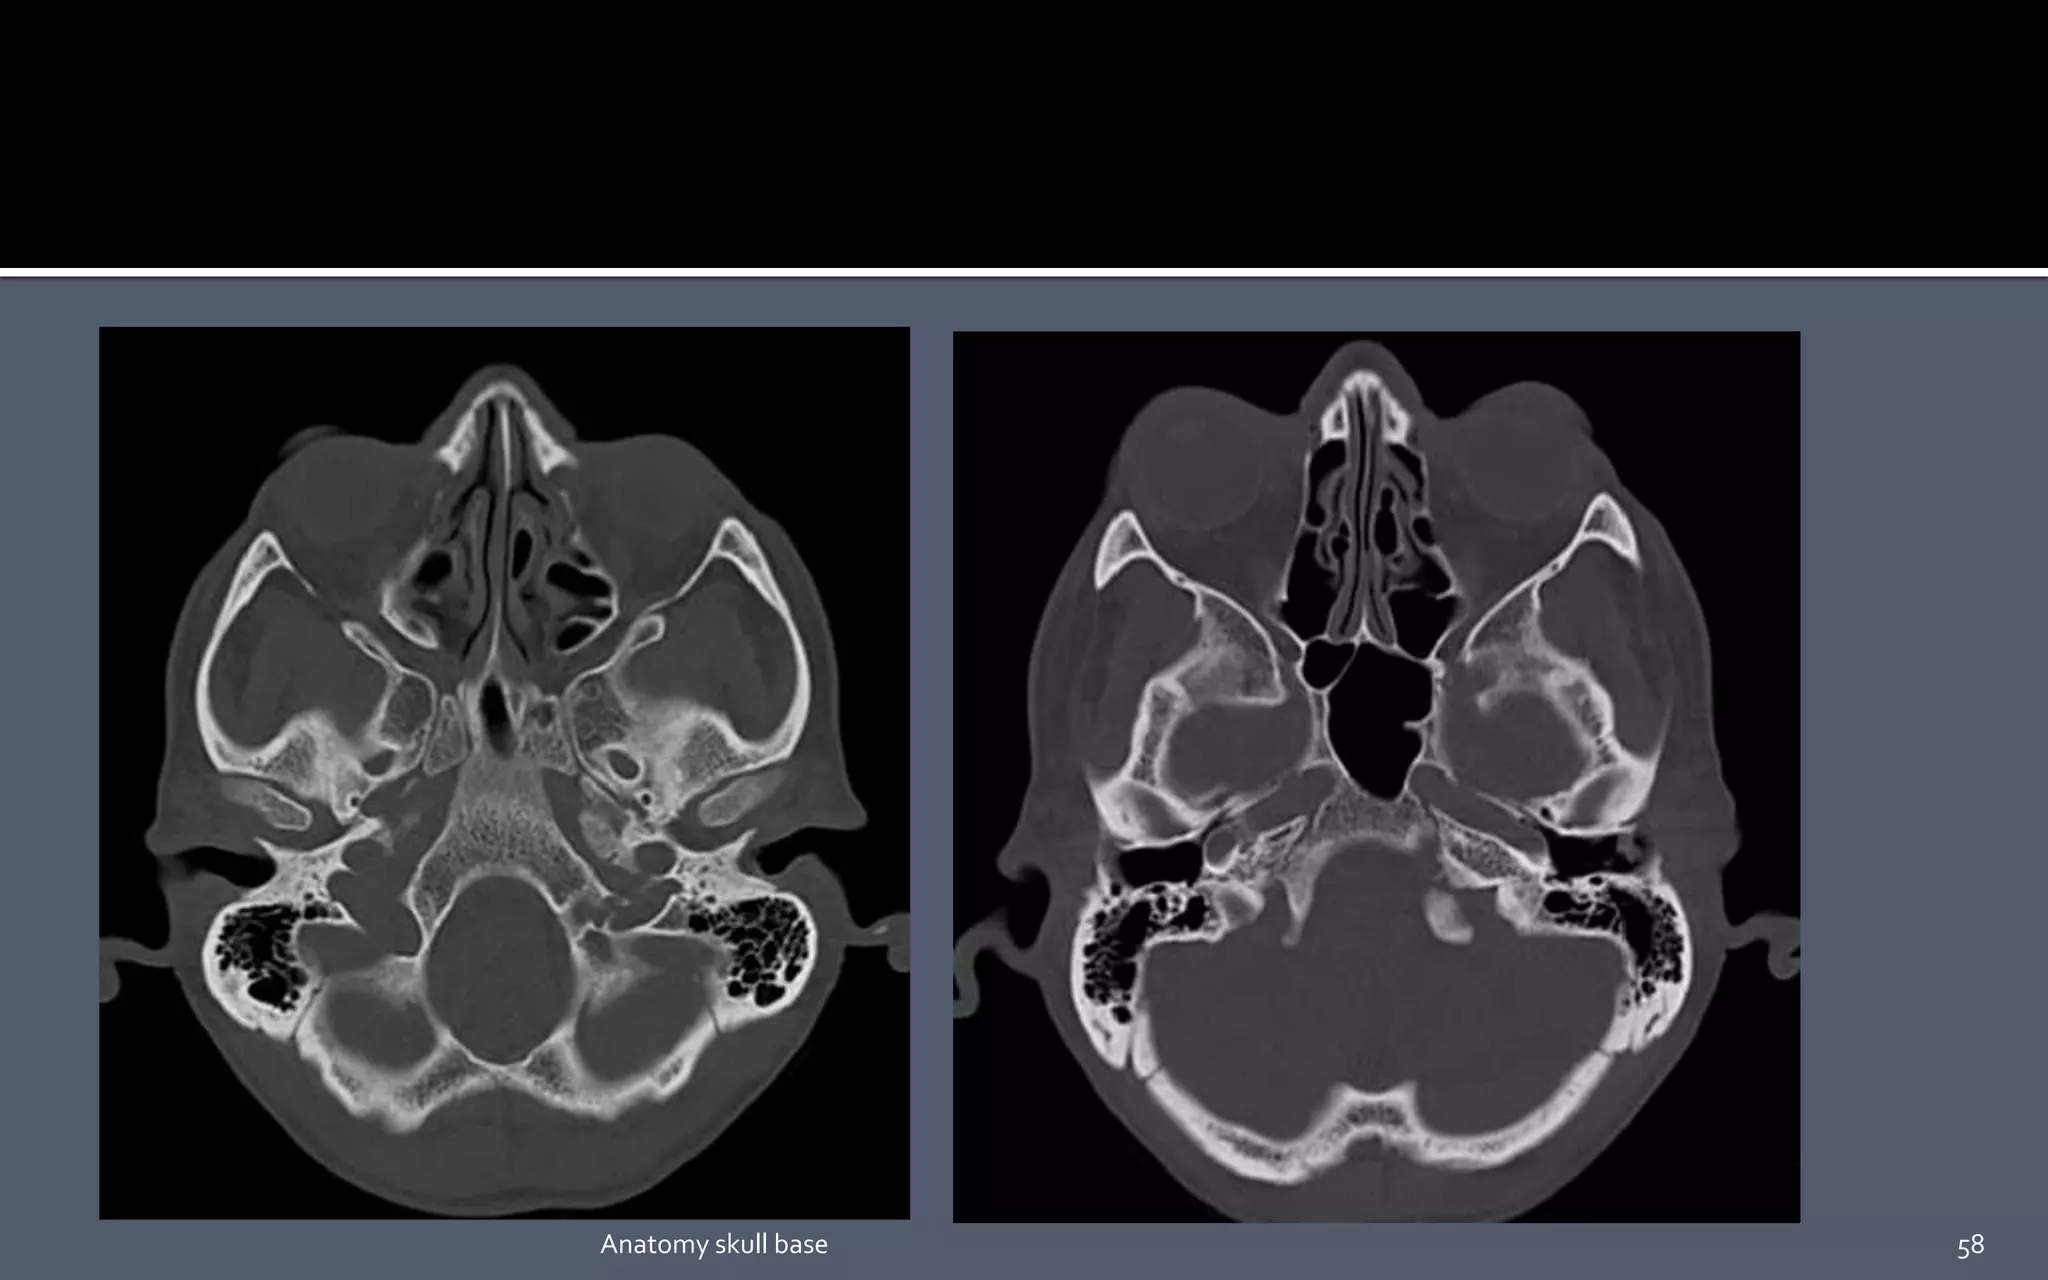

 Parapharyngeal , masticator, carotid, and retropharyngeal spaces are

seen in close contact with the skull base along their cephalad aspect .

58Anatomy skull base